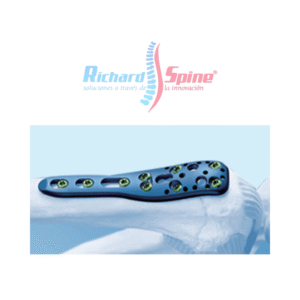

Placa de Bloqueo de Clavícula

- El sistema de placas de bloqueo para la clavícula es un sistema de osteosíntesis de eficacia probada para diversas fracturas de clavícula. La característica especial de este implante es la libre elección de la colocación del tornillo.